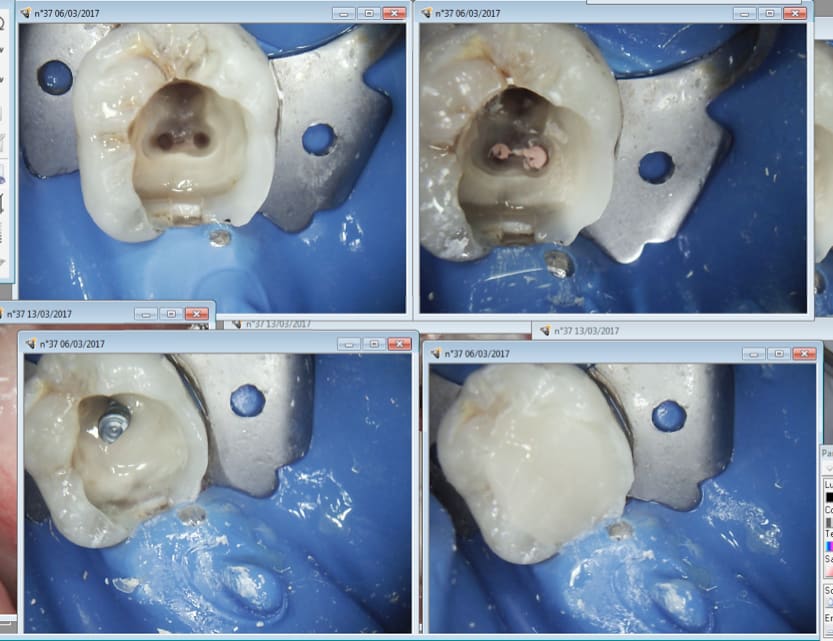

Tiens un SC33. C'est une plaisanterie à faire au luxacore dans la foulée de l'endo. Meme pas besoin de matrice vu que tu couronnes après. Un screw post amalgame te prends plus de temps à fouler et tu as besoin de mettre une matrice.

Dans un exercice normal il aurait fallu faire un onlay. C'est le choix imposé par le système, de faire une couronne mieux remboursée qui délabre pas le fait de faire un inlay core.